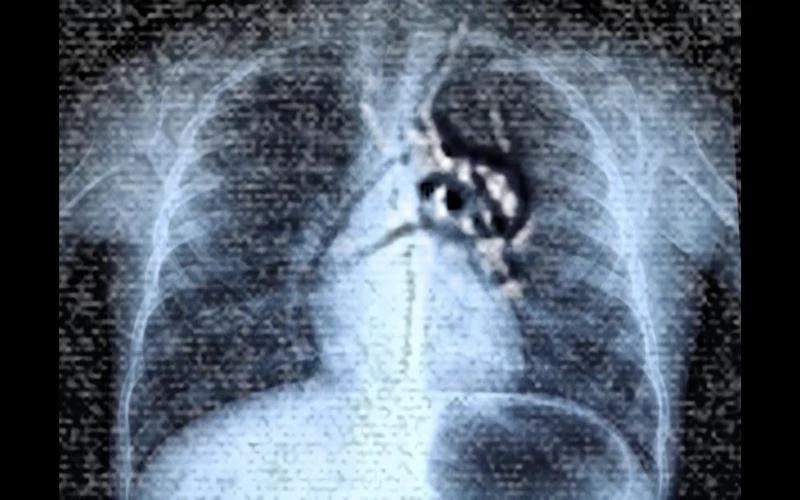

For our issue on The Edges of Conservation, you propose a film with the polysemous title X-hale: It shows an X-ray image of a body that seems to be inhabited by moving organisms, while an intermittent Indonesian voiceover is heard and fragments of a poem in several languages flicker across the screen. What do we see?

Aram Lee : The work started from an exchange I had with a Chinese Indonesian colleague and friend, Francisca Angela, also a resident at Rijksakademie. Both of us had to undergo a medical exam to diagnose tuberculosis when we arrived in the Netherlands. The exam involves medical imagery: You hold a metal plate to your chest and then hold your breath while an X-ray image is made of the lungs. In my work, I combined the medical image of my own body with the images that I had made under the microscope in collaboration with the immunologist Juan J. Garcia Vallej of the Microbes Laboratory at Amsterdam UMC: we analyzed a water droplet from the basement of the Wereldmuseum Amsterdam that had dripped through the museum’s thick foundations. The test revealed 95 living cultures within that droplet. In spite of all the museum’s efforts to seal its walls and shield their collections from the outside world, thousands of living organisms still managed to infiltrate through the walls in microscopic quantities of water. I was interested in the porosity that became apparent in this process. The museum’s goal of creating a conservation space that could effectively separate inside and outside had failed.

LA : In your film, you overlay footage of the living organisms with the X-ray images of your chest – visually, they inhabit your body, as your lungs are circumspectly examined.

AL : The filmic collage combines my personal, lived corporeal experience, which became an object of medical examination, with the microscopic images of the microbes in the water droplets at the museum. It considers the body as a geopolitical locus, as a territory under surveillance to distinguish registered, authorized, and legalized bodies from those considered a danger, or as stowaways, illegal entities, bodies crossing borders without permission.

Both my friend and I had to undergo this mandatory examination, because, when I arrived in 2011, Korea was still one of the countries considered “at risk” from tuberculosis. Indonesia is still on the list, but Korea has been removed. Prior to the exam, people of all origins, wait in a room. One begins to perceive oneself and others as bodies whose status is under scrutiny,  present only to establish if they can be labeled healthy and stay, or not. During the exam, you have to stand with a metal plate against your body, and you are asked to breathe in deeply. Then, you have to hold your breath until you have permission to breathe. I experienced the moment as a suspension of my right to breathe, a suspension that would last the time it took them to decide whether the air that I had brought from Korea was threatening to the Netherlands, or not.

LA : X-ray has repeatedly been used in feminist experimental filmmaking, often to refer to the vulnerability of the body, and its “over-exposure” by technology and patriarchy1. In addition to the fragility of the body as displayed in the x-ray images, in your film you bring the images of the moving microbes to your body. Thereby, you operate a shift, whereby your body and the transparent and “overexposed” medical images of your lungs scrutinized with suspicion by a public health service enacting geographical, bodily controls while attributing degrees of potential danger to them, now becomes the support that allows the microbes to move freely. As if confirming the suspicion of the public health authorities, you visually contaminate your body, inscribing living cultures within it that transgress walls without permission. When watching the film, there is an uncertainty whether these are images of disease gaining space in the human body, or whether they are beneficial parts of the body’s vital processes?

AL : I was intrigued by the resonance between the words “exhale” and “exile”. During the examination, you are asked to hold your breath until the process is complete, then you can exhale and they let you go. While the image is being taken, the flow of breath necessary for any living organism is suspended until the medical staff declares your body free of danger. The examination itself is an experience in the fragility of a body in exile, its vulnerability, subjected to suspicion and investigation. I wanted to work on the stressful and frightening experience of breath suspension. To enhance this experience, in the first part of the video, the soundtrack is solely the sound of breathing in, breathing in, breathing in, breathing in – the breath never flows in the opposite direction. Only at the end of the video is there a change in the direction of breath, and you hear lungs breathing out.

Aram Lee: X-Hale, 2024. Film Still.

Aram Lee: X-Hale. 2024. Film Still.